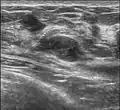

Since both fibroadenomas and breast lumps as a sign of breast cancer can appear similar, it is recommended to perform ultrasound analyses and possibly tissue sampling with subsequent histopathologic analysis in order to make a proper diagnosis. Unlike typical lumps from breast cancer, fibroadenomas are easy to move, with clearly defined edges.[1][2]

Diagnosis

A fibroadenoma is usually diagnosed through clinical examination, ultrasound or mammography, and often a biopsy sample of the lump.[8] Suspicious findings on imaging may result in a person needing a biopsy in order to gain a definitive diagnosis. There are three types of biopsies: fine-needle aspiration, core-needle biopsy and surgical biopsy. The method of biopsy depends on the appearance, size and location of the breast mass.[18]

Fibroadenoma in ultrasound

Fibroadenoma in ultrasound -

The FDA approved cryoablation of a fibroadenoma as a safe, effective, and minimally-invasive alternative to open surgical removal in 2001.[25] During cryoablation, ultrasound imaging is used to guide a probe into the mass of breast tissue. Extremely cold temperatures are then used to destroy the abnormal cells, and over time the cells are reabsorbed into the body.[26] The procedure can be performed as an outpatient surgery using local anesthesia, and leaves substantially less scarring than open surgical procedures and no breast tissue deformation.